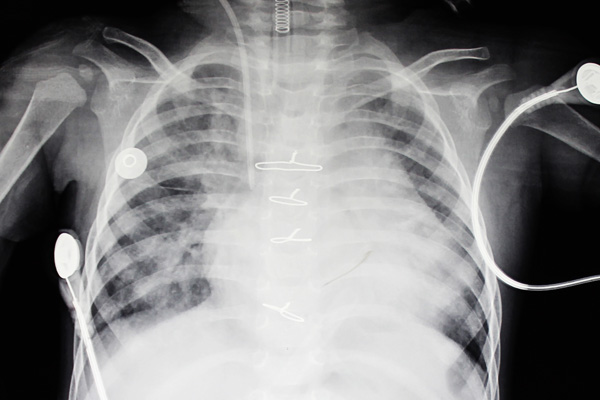

隔日,小鑫怡于下午被推入手术室,经过紧张的几个小时,她的手术顺利完成,安返ICU特护病房。术后第三天,她病情平稳,已经可以拔除气管插管自主呼吸。笔者在小鑫怡术后第四天看到她躺在病床上的样子,显得精神很好,再观察她术后复查的胸片,可看到心脏的大小已经明显小了一圈。小鑫怡出院前三天,即术后第十天时,笔者再去病房探访,她已经从特护病房转到了普通病房,只见小鑫怡的妈妈开心地抱着她坐在床边玩,她水灵灵的眼睛好奇地张望着笔者手中的相机,全然没有病态的模样,令人倍感欣喜。

小鑫怡术后的X光胸片,可以看到心脏小了一圈